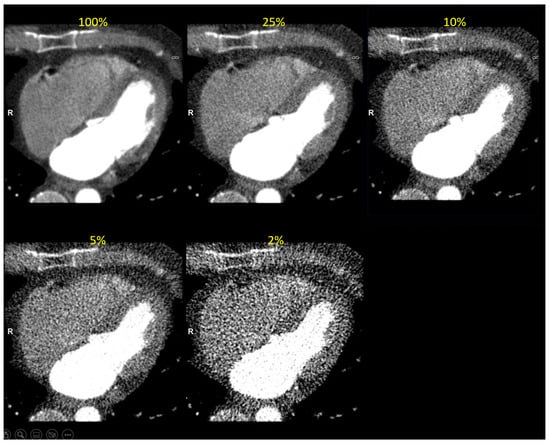

An example of a study simulated at the five dose levels can be seen in Figure 5 and a study with Syngo.Via volume measurement at three dose levels is presented in Figure 6.

Figure 5. Clinical image reconstructed at five simulated dose levels (in end-diastolic phase). The simulated dose level is indicated in yellow font.